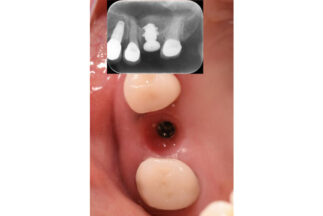

- After

| 治療内容 | 上顎洞底挙上術(トランスクレスタル、水圧)による単独臼歯修復 |